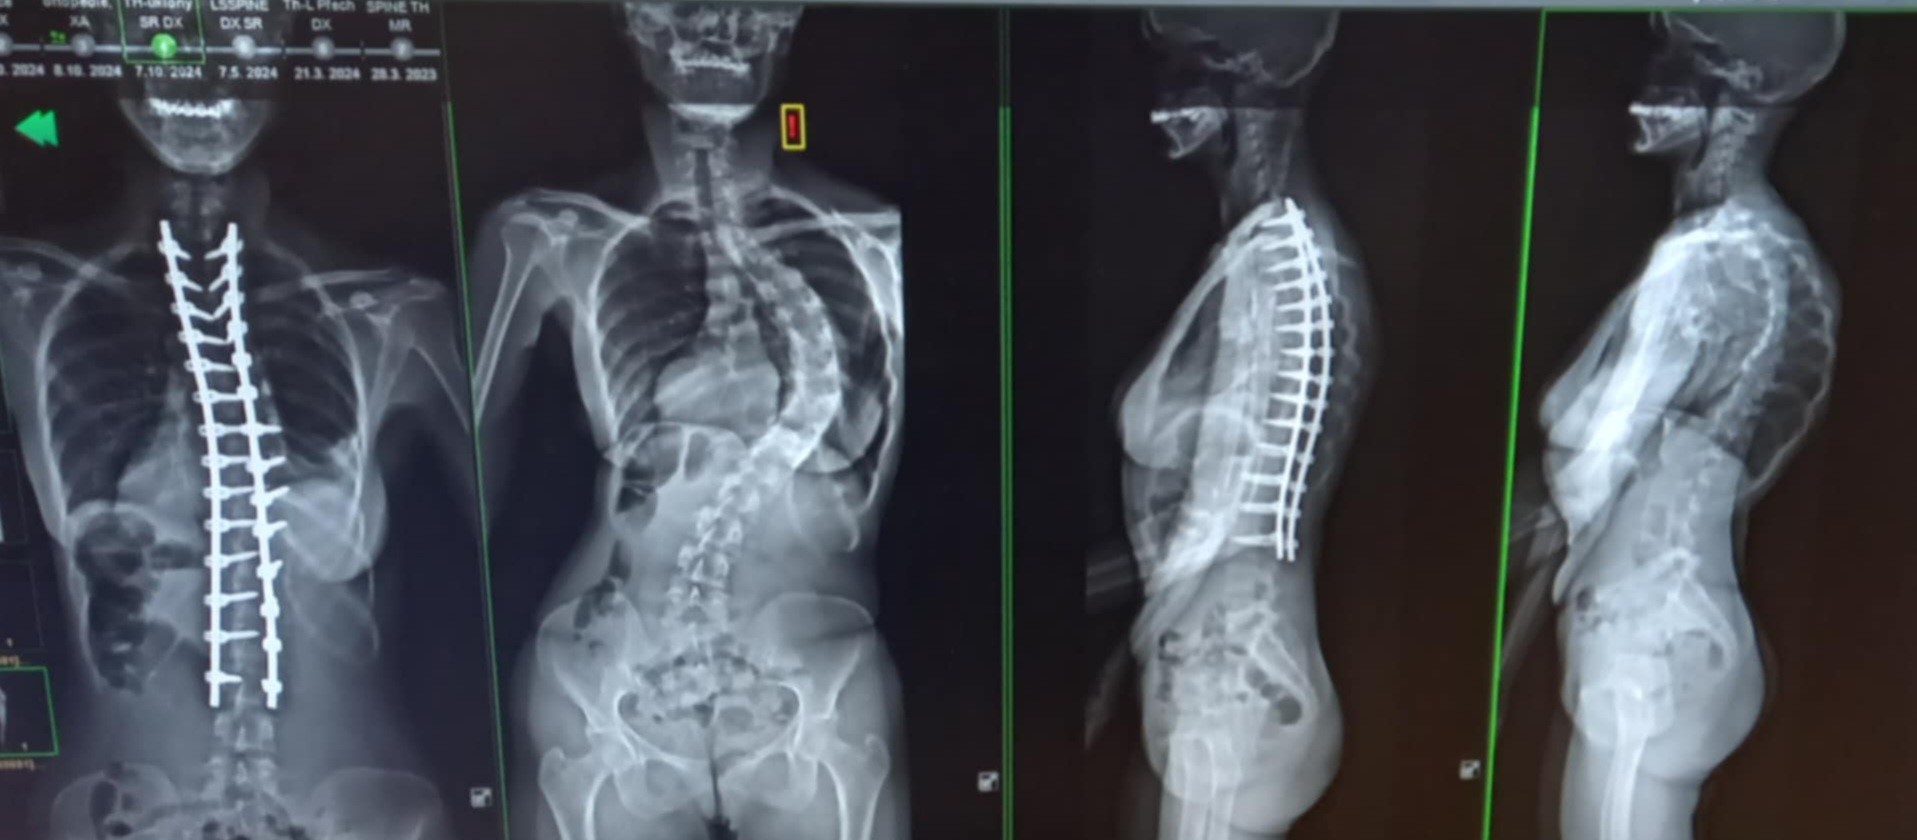

My x-rays showed a right thoracic high 39 degree curve with a left-sided thoracolumbar apex at the TL-junction measuring 52 degrees. In layman's terms, my spine was curved enough at the top and bottom to be eligible for an imminent spinal fusion. I was informed that the surgery involved attaching hooks, wires, screws and two titanium rods to the curved parts of my spine. Then small pieces of bone would be put over my spine so that they would grow together with the spinal bone, fusing it into proper position. I was told my spine would not end up being completely straight and we couldn't fix the rotation of the spine. That would involve covering the entire spine with metal rods, and ultimately I would have no mobility in my back whatsoever.